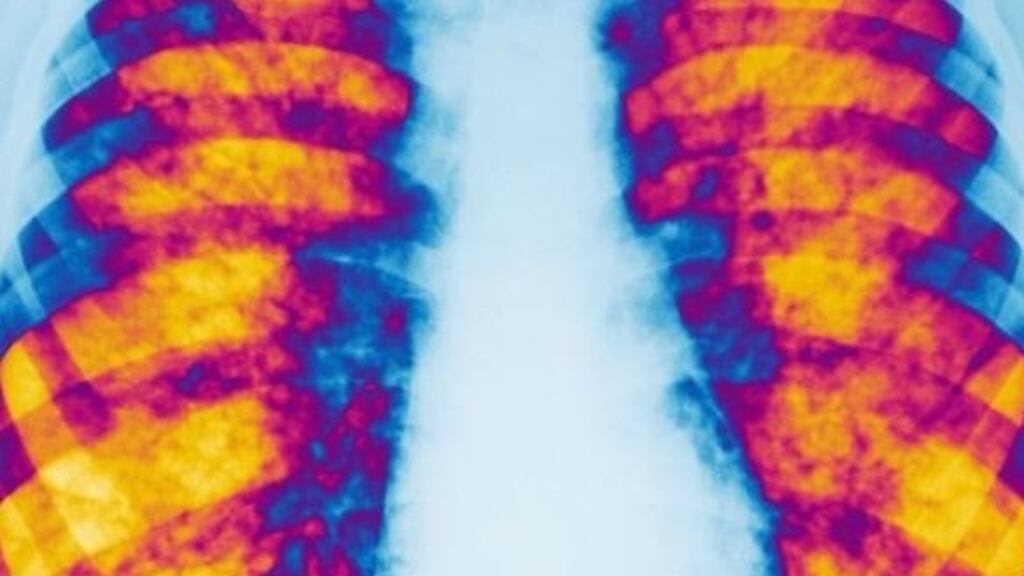

Orkambi, which improves lung function and reduces hospitalisation for CF patients, would cost €160,000 per patient annually, or €400 million for the health service over five years, according to its initial price.